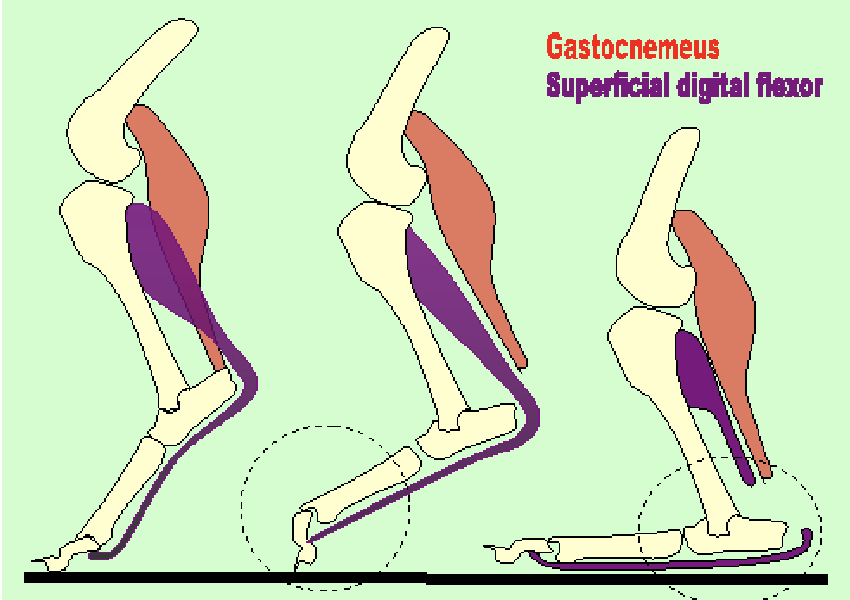

gastrocnemius lacerations, left to right

normal

gastrocnemeus only (plantigrade stance)

gastroc & SDFT → cannot stand